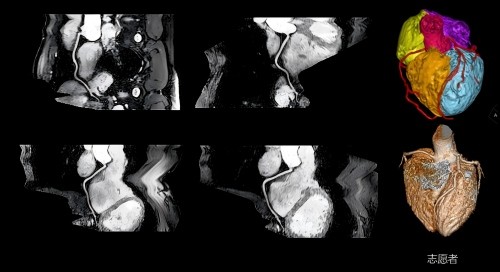

(2)不打药冠脉成像:无电离辐射、无过敏风险,主要适用于冠心病低风险患者及健康人群冠状动脉筛查。

(4)心肌灌注和活性成像:可以准确评估缺血心肌和梗死心肌、纤维化心肌。